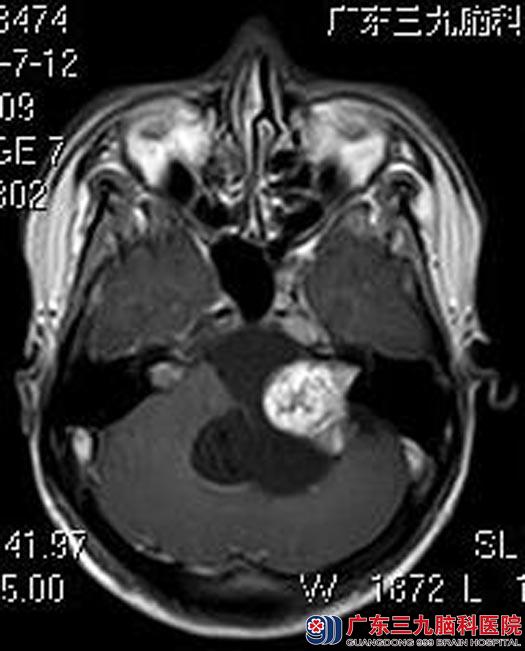

广东三九脑科医院进一步头颅MR检查提示:左侧桥小脑角区巨大囊实性占位性病变,大小约为6.2cm×5.9cm×5.8cm;邻近基底动脉受压且部分被包绕,邻近脑组织明显受压变形,四脑室受压变窄,考虑听神经瘤;头颅CTA检查提示:左侧桥脑脑角区囊实性占位性病变,实性部分血供丰富,左侧小脑后下动脉及左侧椎动脉、基底动脉受压移位。